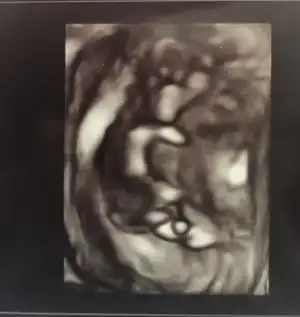

İlk resim 4 boyutlu denilen ultrason(4. Boyut zaman ama olsun :D)

İkincisi burun kemiği ölçümü

Üçüncüsü tüm vucüt